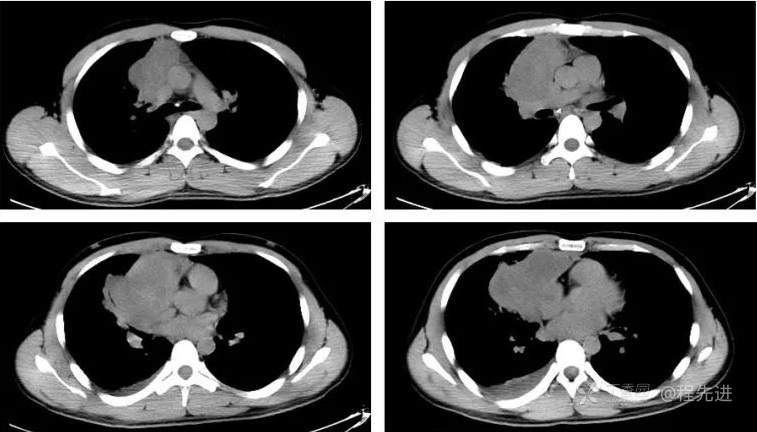

CT平扫